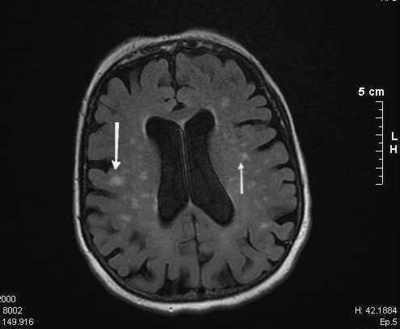

Question 4

Question

La enfermedad de Creutzfeldt-Jakob:

Image:

003f0c53-d2fc-4ca1-b794-dd3ce9d85b86 (image/jpg)

Answer

A- La enfermedad de Creutzfeldt-Jakob es una encefalitis espongiforme.

B- La enfermedad se debe a un organismo infeccioso, llamado prión.

C- Se encuentra una atrofia cortical cerebral diseminada en los individuos afectados.

D- Se produce una reacción inflamatoria aguda.

E- Los pacientes desarrollan una demencia de rápida progresión-